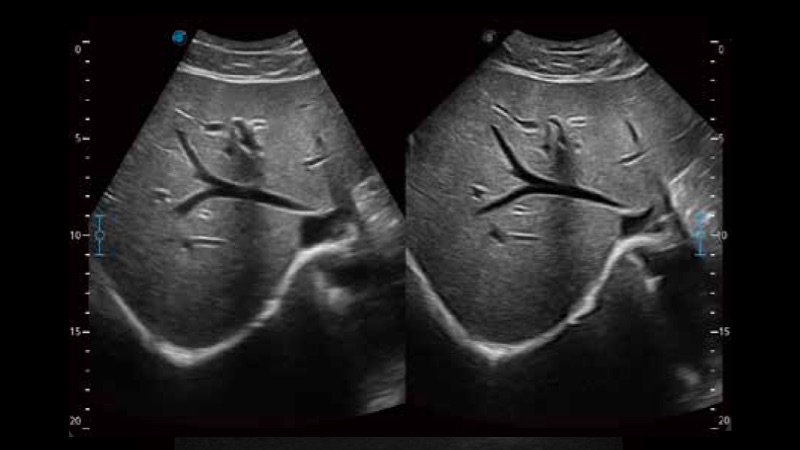

临床图像

扩展成像技术

凸阵、线阵和相控阵探头进行实时扫描时,开启扩展成像模式,可以扩展超声图像视野,以便更完整地查看大的病灶或组织器官的解剖结构。